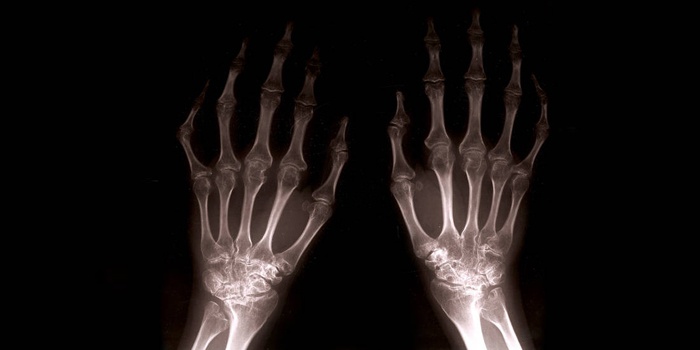

- Поверхность фаланг пальцев, оставшись без смазки, разрушается. Происходит «перерождение» костной ткани, образуются остеофиты – наросты, заметные на рентгеновском снимке.

- Характеризуется неподвижностью суставов, которые сильно разрушены. Остеофиты наглядно видны, образуя узелковые наросты: проксимальные (сбоку сустава) – Бушара, дистальные – Гебердена.

- Рентген. На основании данных рентгенографии доктор устанавливает степень поражения мелких суставов и стадию развития болезни.

Для правильной диагностики необходимо провести рентген.

- рентгенологическое исследование (смотрят на деформацию сустава, разрастания костных отростков, сужение щели между суставами);

Боль в суставе кисти может иметь своей причиной артроз – заболевание, в основе которого находится преждевременное старение и изнашивание хряща, который покрывает сочленения костей, образующих сустав. Пораженный хрящ начинает истончаться, растрескиваться, обезвоживаться и терять свои амортизационные свойства. Проявлением этого и служит болевой синдром. С течением времени на суставной поверхности начинают появляться остеофиты – шипообразные костные разрастания, которые изменяют конфигурацию сустава, вызывают его деформацию, и травмируют окружающие тканевые структуры, вызывая усиление боли. Почти всегда эта патология является уделом людей пожилого возраста, хотя встречаются и семейные, наследственные формы остеоартроза, при которых начало заболевания отмечается в юношеском или даже в детском возрасте.

В диагностике остеоартроза важнейшую роль играет рентгенологическое исследование. На рентгенографии определяют наличие костных разрастаний, сужений суставной щели, уплощений и деформаций хрящевых поверхностей суставов, а также разрушений самой костной ткани. Лечение остеоартроза начинают со снятия воспаления и болевого синдрома при помощи стероидных и нестероидных противовоспалительных препаратов. Применяют также и средства, повышающие защитные свойства хрящей. Но основное место в терапии данного заболевания занимает лечебная физкультура, физиотерапевтические процедуры и санаторно-курортное лечение.